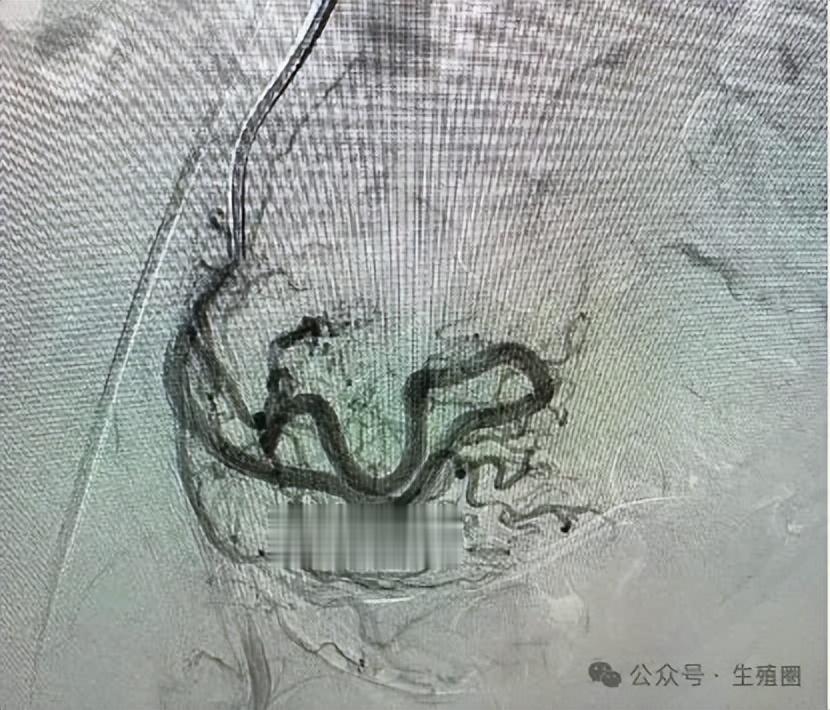

他们决定为她行动脉栓塞术,这是一种微创介入治疗。医生从患者大腿根部的血管插入一根细导管,在X光引导下,将导管精确送到给这个血管团供血的子宫动脉分支。

然后注入一种叫明胶海绵颗粒的栓塞剂,这些颗粒就像无数小沙子,随着血流堵住畸形血管团的供血血管,使其内部形成血栓,最终让这个血管团萎缩消失。

手术非常成功,几个月后复查血管核磁共振,显示那个血管团已经显著缩小,血流信号几乎消失。